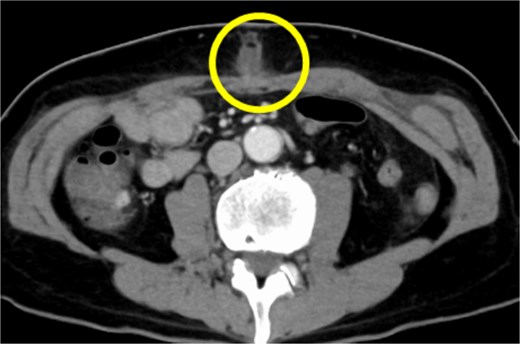

A 54-year-old Japanese male patient, previously healthy, was diagnosed with esophageal cancer (cT1N1M0, cStage I). He underwent radical chemoradiotherapy (FP-RT, 50.4 Gy/28Fr); however, the primary lesion persisted. Subsequently, he underwent a robot-assisted thoracoscopic subtotal salvage esophagectomy lasting for 9 h and 24 min, with a blood loss of 130 mL. Postoperative pathological examination revealed ypT2N3M0, ypStage IV A. The patient developed suspected pneumonia on postoperative day one and was treated with antibiotics. Despite a change in antibiotics, his fever persisted, prompting further investigation and treatment adjustments. Although there were no overt signs of cough or pneumonia, covert aspiration pneumonia was considered, and treatment with broad-spectrum antibiotics was initiated on postoperative day 14. Tests for various collagen disease markers and cytomegalovirus antigens revealed negative results, ruling out infectious endocarditis. Despite the negative cultures, the patient’s fever persisted without improvement in C-reactive protein levels. Regular blood cultures were consistently negative. Sputum cultures were also performed, revealing only common oral flora. Consequently, treatment with broad-spectrum antibiotics was continued. On postoperative day 24, the patient developed surgical site infection (SSI) at the midline incision (Fig. 1). Wound debridement was performed, resulting in a gradual decrease in fever frequency; the patient was discharged thereafter.

CT findings suggestive of an SSI. The circles indicate abscesses.